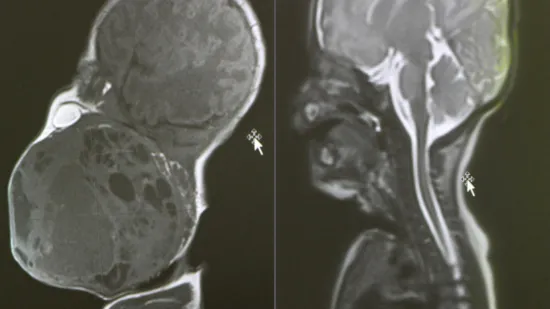

Nakon nekoliko mjeseci, dva tumora u mozgu više nisu bila prisutna.

„Doktorica je pogledala nalaze i tiho rekla – nema više ničega. Nisam mogla povjerovati… suze su samo krenule“, prisjetila se Zdenka, pacijentica koja je prošla CAR-T terapiju za RTL.